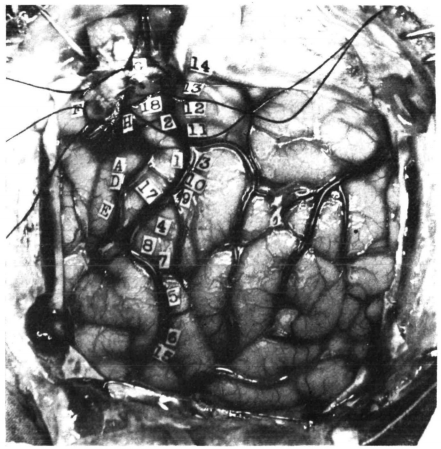

在每次手术过程中,彭菲尔德会在患者的大脑上放置编号的小标签,并详细记录通过电刺激特定区域所触发的具体反应(见下图):

![]()

▷图3.彭菲尔德代针对癫痫病患的脑部电极刺激的实验,图中的每个数字对应于彭菲尔德映射的特定大脑功能和感觉。具体描述如下。图源:American Neurological Association

> 14. 从膝盖到右脚有刺痛感,无麻木。

> 13. 整条右腿感到麻木,不包括脚。

> 12. 右侧手腕下边缘感到麻木。

> 11. 右肩感到麻木。

> 3. 手和前臂感到麻木,直至前臂上方。

> 10. 第五指或小指有刺痛感。

> 9. 前三个手指有刺痛感。

> 4. 四个手指(不包括拇指)感到像电击后的麻木。

> 8. 拇指感到运动的感觉;但看不到任何运动的证据。

> 7. 同8。

> 5. 舌头右侧感到麻木。

> 6. 舌头右侧,尤其是尖端,有刺痛感。

> 15. 舌头有刺痛感,伴随上下振动运动。

> 16. 舌根后侧中线部分感到麻木。

> 中央前回从上到下:

> (G) 膝盖的屈曲。

> 18. 手臂和手轻微的抽搐像是电击,并感觉想要移动它们。

> 2. 肩膀向上耸动;不感觉像是发作。

> (H) 右臂、肩膀、前臂的阵挛运动,躯干无运动。

> (A) 手腕、肘部和手的极端屈曲。

> (D) 手的闭合和手腕的屈曲,像是发作。

> 17. 感觉自己将要发作,手臂和前臂屈曲,手腕伸展。

> (E) 手的轻微闭合;刺激后脑部局部潮红;这一动作在强度为24时重复。发红后随之而来的是苍白几秒钟。

> (B) 病人表示他无法控制地闭上右眼,但实际上他闭上了两只眼睛。

> (C) 发出了一点声音;发声。这一动作重复了两次。病人说他控制不住。这与上下唇的运动相关,两边相等……